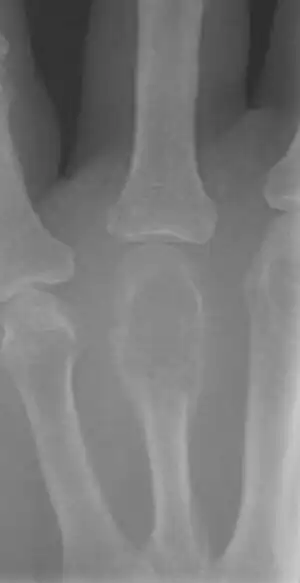

| Other names: Osteoclastoma | |

| X-ray of a giant-cell bone tumor in the head of the fourth metacarpal of the left hand | |